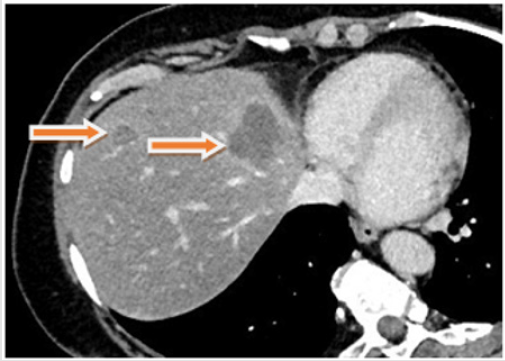

Figure 1: CT at time of reevaluation after systemic chemotherapy showing the liver metastases and the the primary tumor in the right hemicolon (arrows).

A 60-year-old female patient with an advanced right sided colon cancer with synchronous multiple liver metastases was admitted to the University Clinic for General, Visceral, Vascular and Transplant Surgery, University of Magdeburg, for surgical evaluation after administration of palliative, systemic chemotherapy combining leucovorin calcium (folinic acid), 5FU and irinotecan hydrochloride (FOLFIRI) and Bevacicumab over six months. After performing a computed tomography (CT, Figures 1-3) and complementary diagnostics through Magnet-Resonance Imaging (MRI) there was a partial response of the primary tumor mass in the right hemicolon and of the multiple liver metastases, which were finally located in the left liver lobe. After thorough examination of all oncologic aspects in our interdisciplinary tumor conference and due to partial response after systemic chemotherapy and the good general condition of the patient we decided for robotic right hemicolectomy and left hemihepatectomy simultaneously.